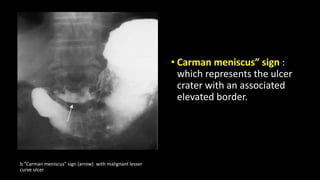

• Carman meniscus” sign :

which represents the ulcer

crater with an associated

elevated border.

b “Carman meniscus” sign (arrow) with malignant lesser

curve ulcer